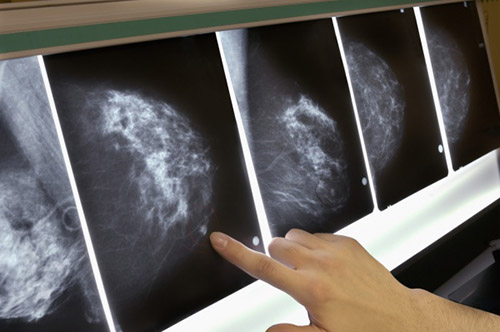

Başka kanser türlerinde olduğu gibi meme kanserinde de erken teşhis çok önemli ve hayat kurtarıcı olduğu için dünyanın birçok ülkesinde mamografi ile taramalar yapılıyor.

Türk Radyoloji Derneği (TRD) de kadınlarımıza 40’ tan 70 yaşına kadar her sene mamografi çektirmeleri tavsiyesinde bulunuyor ama erken teşhis için mamografilerin gerekli olup olmadığı, hangi yaştan itibaren ve hangi sıklıkla yapılmasının doğru olduğu konusunda farklı görüşler var.

Mamografilerin meme kanserinden ölümleri azaltmada sanıldığı kadar etkili olmadığını, hatta zararının daha fazla olabileceğini ortaya koyan çalışmaların sayısı giderek artıyor.

Meme kanserinin erken tanısında tarama amaçlı kullanılabilecek mamografiye daha üstün bir teknik geliştirilmemiştir. Genel olarak veriler değerlendirildiğinde mamografi taraması meme kanserinden ölümü yüzde 25-30 arasında azaltmaktadır.”

Öncelikle, mamografiler sayesinde kanserden ölümlerin yüzde 25-30 oranında azaldığını gösteren çalışmaların onlarca sene önce yapıldığını hatırlatmak isterim.